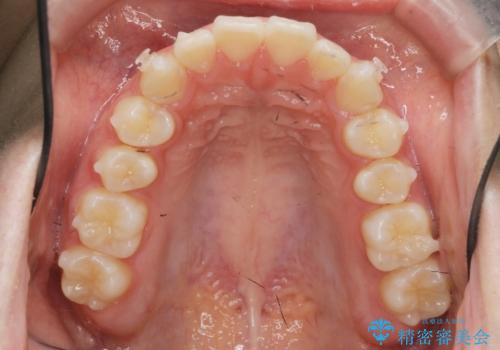

矯正治療を途中でやめてしまった、途中からの治療希望

- 他院での矯正治療中に行かなくなってしまい、装置をつけたまま矯正治療の続きを希望され来院されました。

マウスピースでは並べることが難しい左下の奥歯を部分ワイヤー矯正で並べたのち、マウスピース矯正装置インビザラインで歯並びを整えていきます。